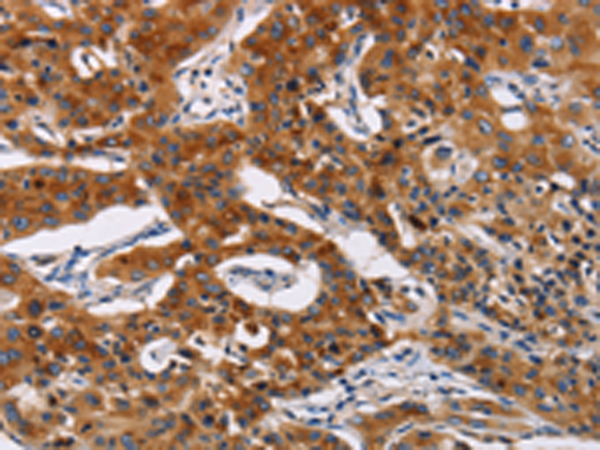

分类: 科研抗体货号: P00543别名: DUP; FAP4; MRP1应用: WB,IHC反应种属: Human, Mouse